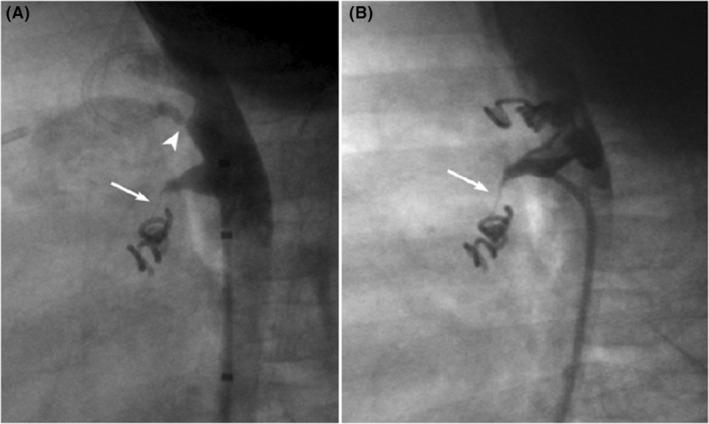

We present a case report of a trisomy 21 infant with atrial and ventricular septal defects and small patent ductus arteriosus (PDA) complicated by the presence of descending aorta to right atrial (RA) fistula with large left to right shunt leading to rapid increase in pulmonary vascular resistance. Transcatheter occlusion of the fistula followed by closure of the PDA with Nit-Occlud coil systems led to decreased pulmonary pressure and resistance permitting successful surgical repair of the patient's intracardiac defects with good outcome over 3 years of follow-up. Descending aorta to RA fistula is a rare and distinct clinical entity mimicking PDA and its correct diagnosis and treatment, especially in the presence of other congenital heart defects, is very important as it may lead to rapid development of pulmonary vascular disease.

我们报告一例21三体综合征婴儿,患有房间隔和室间隔缺损以及小型动脉导管未闭(PDA),并合并降主动脉至右心房瘘,存在大量左向右分流,导致肺血管阻力迅速增加。经导管封堵瘘口,随后使用Nit-Occlud线圈系统封堵PDA,导致肺动脉压力和阻力降低,使患者心脏内缺损得以成功手术修复,随访3年效果良好。降主动脉至右心房瘘是一种罕见且独特的临床病症,类似于PDA,其正确的诊断和治疗非常重要,尤其是在合并其他先天性心脏缺陷的情况下,因为它可能导致肺血管疾病迅速发展。